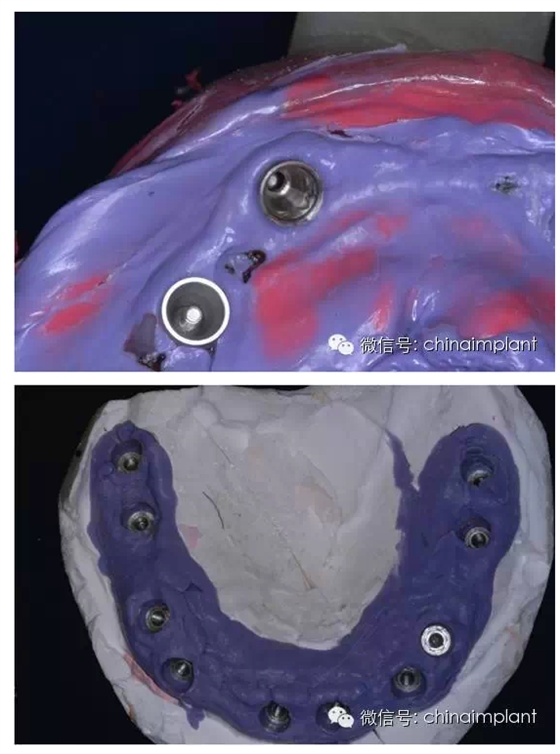

此案例為術(shù)后兩周戴臨時(shí)牙。過去因?yàn)閾?dān)心感染的問題,一個(gè)月以內(nèi)帶臨時(shí)牙也叫做即刻負(fù)重或者早期負(fù)重。(現(xiàn)在當(dāng)天戴臨時(shí)牙(即刻復(fù)重)的情況也非常常見).